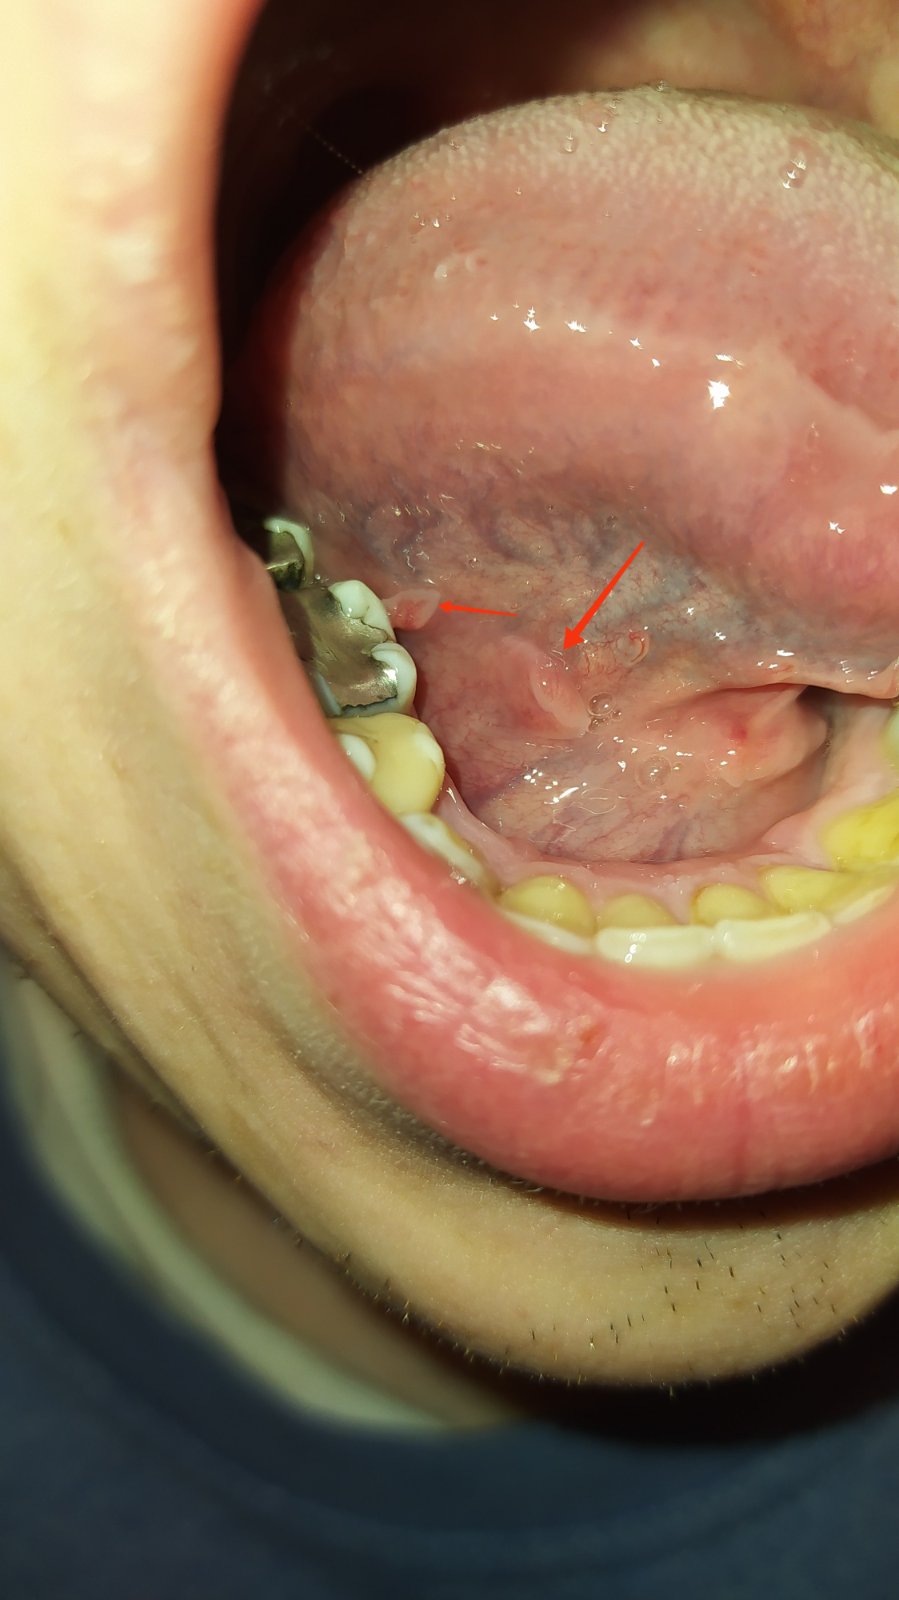

Výrastky pod jazykom

@oli18 vraví že pred 2 mesiacmi tam neboli, až keď cítil taký divný pocit pod jazykom tak ich zbadal. Vyzerá to ale neprirodzene.

@katkazocele necj nestresuje.ani plomby tam nemal ked zuby narastli.terszma inak zuby proste sliznica sa trie ,prisposobuje rastie tam kam moze.zapolove zmeny tam nie su.mize skonzultovat do zubarom.ake nic nenormalne to nie je

Lekara nie, take vyrastky ma kazdy, ma to tam byt. Len si to asi doteraz nevsimol, ze to tam ma